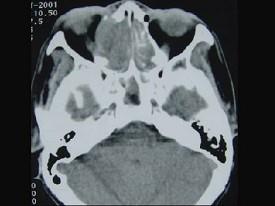

女性,53岁,右侧鼻腔流血近一年,近来头痛,行CT检查如图所示,请选择正确的答案 ( )

• A.鼻腔内血管瘤

• B.鼻腔内息肉

• C.鼻腔癌

• D.鼻腔炎性假瘤

• E.副鼻窦炎

答案: C